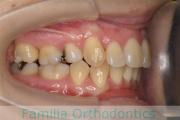

No.22V-449

- 主な症状:

- 上顎前突

- その他の症状:

- 叢生

- 年齢:

- 14歳

- 性別:

- 男性

- 抜歯部位

- 上:

- 44

- 下:

- 8448

- 主な使用装置:

- FEA

- 治療にかかった費用:

- 87万円

歯並びをきれいにしたいということで来院されました。上下左右から小臼歯を抜歯して、マルチブラケット法を行っています。2年弱、25回程度の通院が必要でした。

かなり強い叢生(でこぼこ、凹凸、ガタガタ)ですので、保定をしっかりしないと後戻りのリスクがあります。